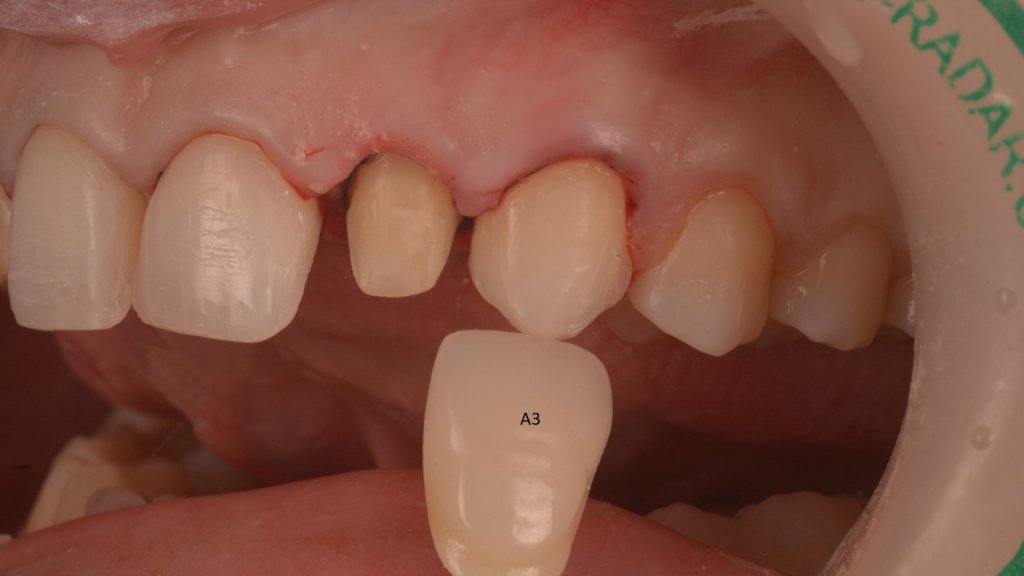

Y vamos de Azul (NIC TONE) sin linea de terminación, sufrimos el doble..no tenemos donde agarrar el Clamp y sobre todo donde realmente termina la carilla…

Voy siempre de 2 en 2, claramente cemento antes las Coronas, que me ayudaran a «clampar» y luego las carillas. Pero normalmente empiezo con los laterales que están en el medio y suelen robar el espacio a los otros

No me asusta esta ligera inflamación, al revés se que están pasando cosas buenas, la encía se esta estabilizando y engordando según los principios de la técnica BOPT. Así que tengo tiempo para disfrutar simplemente del trabajazo de Nacho.